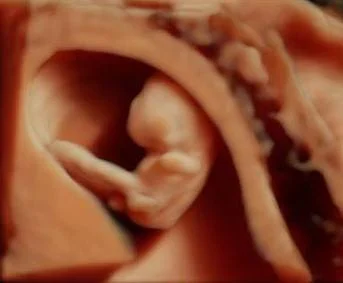

CRL measurement

3D 10 weeks